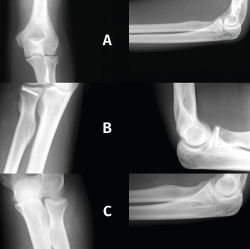

Los estudios de imagen para evaluar un codo rígido deben ser, en primer lugar, unas radiografías simples, que incluyan proyecciones anteroposterior, lateral y 2 oblicuas. Si se requieren más detalles de la superficie articular, se debe realizar una tomografía computarizada (TC) del codo con reconstrucciones tridimensionales que ayudará en la planificación quirúrgica para eliminar osteofitos y osificaciones heterotópicas (Figura 2).

Figura 2. Fibrosis articular, degeneración del cartílago y presencia de cuerpos libres no calcificados.

La resonancia magnética (RM) puede ser útil para valorar el cartílago articular, la fibrosis articular y periarticular, el estado ligamentoso y la presencia de cuerpos libres no calcificados (Figura 3).

Figura 3. Fibrosis articular, imagen de resonancia magnética.